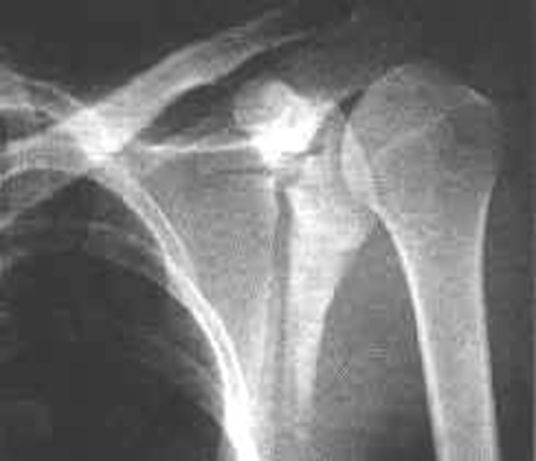

肩锁关节脱位

疼痛科怎么理疗疼痛科医生、康复理疗科医生、针刀针灸医生应掌握的常见骨科疾病X光片_https://www.jmylbn.com_新闻资讯_第5张

前脱位,前内脱位,后脱位。